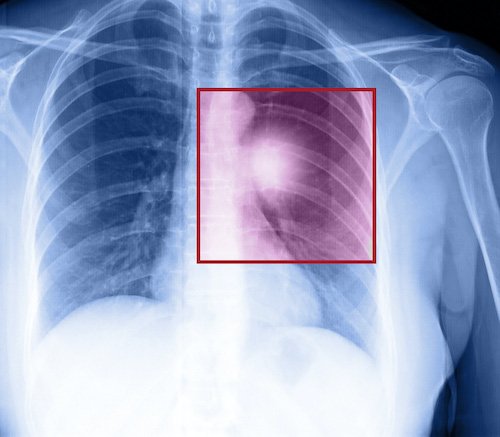

İleri evre akciğer kanserinde umut artıyor Akciğer kanseri tedavisindeki yenilikler, özellikle kanser evresi ilerlemiş hastalarda, yüz güldüren sonuçlar alınmasını sağlıyor. Kansere bağlı ölümlerde ülkemizde, erkeklerde birinci, kadınlarda ise ikinci olan akciğer kanseri; öksürük, kanlı balgam, nefes darlığı, kilo kaybı ve göğüs ağrısı ile kendini gösteriyor. Yüzde 85-90’ı sigara kullanımına bağlı gelişen akciğer kanseri tedavisinde yaşanan